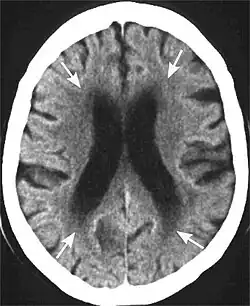

Leukoaraiosis is a particular abnormal change in appearance of white matter near the lateral ventricles. It is often seen in aged individuals, but sometimes in young adults.[1][2] On MRI, leukoaraiosis changes appear as white matter hyperintensities (WMHs) in T2 FLAIR images.[3][4] On CT scans, leukoaraiosis appears as hypodense periventricular white-matter lesions.[5]

The term "leukoaraiosis" was coined in 1986[6][7] by Hachinski, Potter, and Merskey as a descriptive term for rarefaction ("araiosis") of the white matter, showing up as decreased density on CT and increased signal intensity on T2/FLAIR sequences (white matter hyperintensities) performed as part of MRI brain scans.

These white matter changes are also commonly referred to as periventricular white matter disease, or white matter hyperintensities (WMH), due to their bright white appearance on T2 MRI scans. Many patients can have leukoaraiosis without any associated clinical abnormality. However, underlying vascular mechanisms are suspected to be the cause of the imaging findings. Hypertension, smoking, diabetes,[3] hyperhomocysteinemia, and heart diseases are all risk factors for leukoaraiosis.